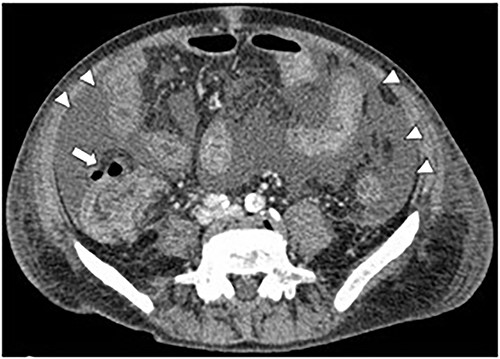

A 71-year-old man was diagnosed with advanced non-small cell lung carcinoma and pleura and lymph node metastasis. He received carboplatin, paclitaxel, bevacizumab and atezolizumab every 3 weeks as first-line chemotherapy for 4 months. As the pleural dissemination worsened, docetaxel and ramucirumab were administered as second-line treatment. The patient had three episodes of ileocecal diverticulitis following chemotherapy, all of which were treated conservatively with antimicrobials and fasting therapy. The diverticulitis episodes and computed tomography (CT) images are shown in Figs 1 and 2a–c. During the fourth diverticulitis episode, the patient presented with fever and abdominal pain, worsening after 5 days. Physical examination revealed tenderness and rigidity throughout the abdomen. Vital signs were stable, but body temperature was 37.7°C. Laboratory data showed inflammation with a white blood cell (WBC) count of 21 400/μL and a C-reactive protein (CRP) level of 23.8 mg/dL. Abdominal CT imaging showed ascites and intra-abdominal free air around the right-side colon (Fig. 3). Hence, we suspected a right-side colon perforation with acute diffuse peritonitis and performed an emergency laparotomy with a midline incision. Surveying the small bowel revealed that ileal perforation occurred only a few centimeters proximal to the ileocolic valve (Fig. 4). The patient underwent ileocecal resection, ileostomy and a colonic mucous fistula.

CT image of the ileocecal diverticulitis. The image shows that ileocecal diverticulitis (arrows) has occurred three times (a–c) until the diverticular perforation.